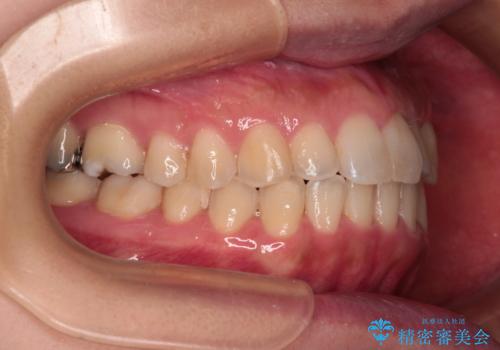

- 前歯の捻れを気にして来院された患者様です。

上顎前歯が捻れて前方に飛び出しており、下顎前歯もそれに沿うようにデコボコとなっていました。

IPR(歯と歯の間を削る処置)によりスペースを獲得して上下前歯のデコボコを改善し、インビザラインにて矯正治療を行うこととしました。

捻れていた前歯の形態が、先端が欠けていたり、一部むし歯処置により左右非対称の形態となっていたため、なかなかゴールが定まらず、治療期間がかかってしまいました。